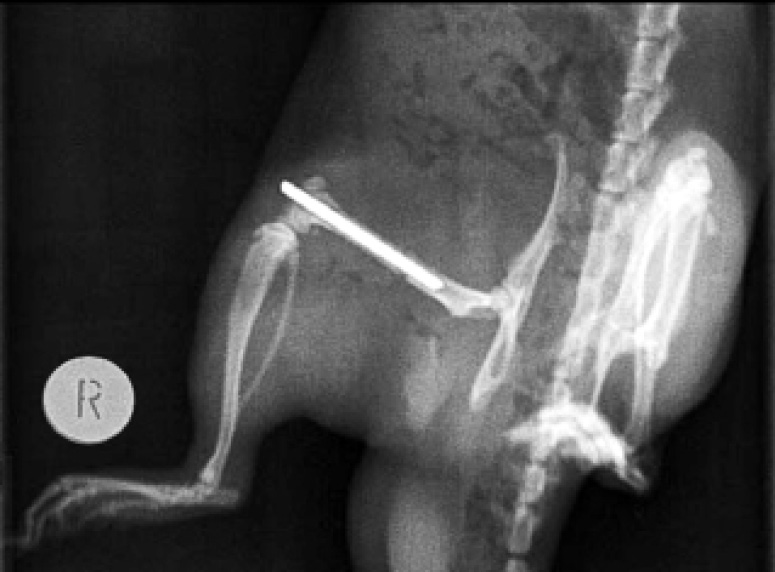

Контрольную рентгенографию области таза и задних конечностей первый раз выполняли после завершения интрамедуллярного остеосинтеза непосредственно после операции, второй раз – у умерших животных в день гибели (в среднем на 8–9-е сутки), у выживших – на 30-е сутки.

Крысам контрольной группы, состоявшей из 10 животных, наносили перелом бедренной кости. Диафизарный перелом бедренной кости фиксировали спицей Киршнера до удовлетворительного сопоставления отломков. Критерием удовлетворительной репозиции являлось сопоставление отломков, расстояние между которыми не превышало 1 мм (рис. 1).

Рис. 1. Внешний вид диафизарного перелома бедренной кости у крысы после интрамедуллярного остеосинтеза

Рентгенограммы выполняли в 2 проекциях (передней и боковой) на аппарате «Artis Zee» фирмы «Siemens», пленке РМ-В форматом 400×200 мм, в режиме 50 кV с экспозицией 0,2 с.

Консолидацию костных отломков оценивали по результатам рентгенологического исследования. Критериями срастания перелома являлись диастаз между проксимальным и дистальным отломками, положение спицы Киршнера в костно-мозговом канале бедренной кости и формирование костной мозоли.

У выживших животных признаки консолидации перелома отмечались начиная с 21-х суток (рис. 2). Однако к исходу 30-х суток несросшиеся диафизарные переломы (миграция спицы Киршнера, диастаз между проксимальным и дистальным костными фрагментами, смещение костных отломков) выявлялись в 15–20% случаев. В среднем сроки консолидации перелома в экспериментальной группе составили 30 суток.

Рис. 2. Рентгенограмма правой задней конечности крысы (30 суток после операции). Металлоостеосинтез (спицей Киршнера) диафизарного перелома бедренной кости. Замедленная консолидация перелома